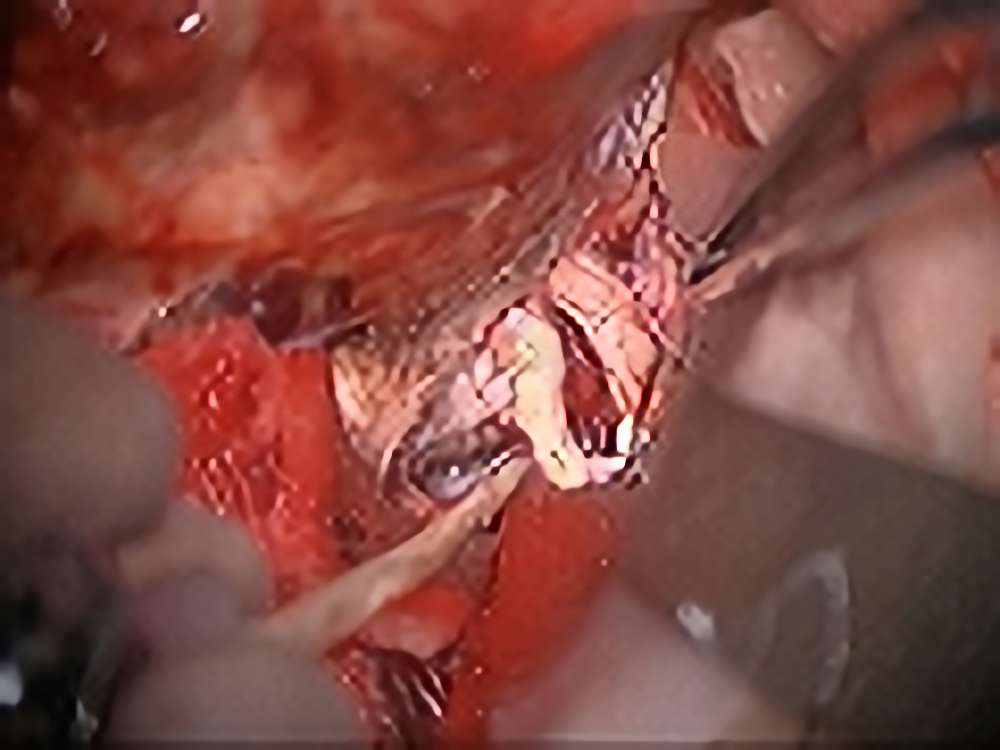

聴神経鞘腫

No.’14_1 手術前1

No.’14_1 摘出 前

No.’14_1 摘出 後